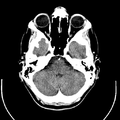

تصوير مقطعي حاسوبي

التصوير المَقْطَعي الحاسوبيX-ray computed tomography نظام تصوير بالأشعة السينية، يُسْتخدم لتصوير مختلف أجزاء الجسم مثل الرأس والقلب والبطن. ويستعين الأطباء بالتصوير المقطعي الحاسوبي على تشخيص الأمراض وعلاجها. وتسمى هذه التقنية أيضًا التصوير المقطعي المحوسب أو التصوير المقطعي المحوري المحوسب.

معرض الصور